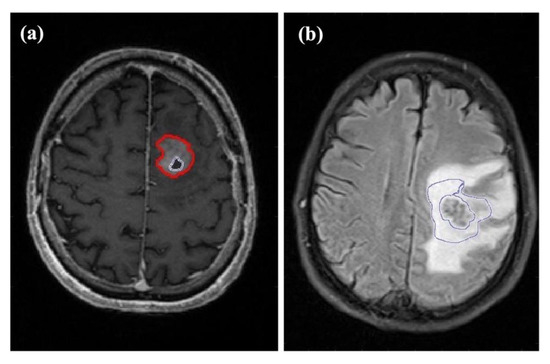

2.2. Image Acquisition

2.3. Image Processing